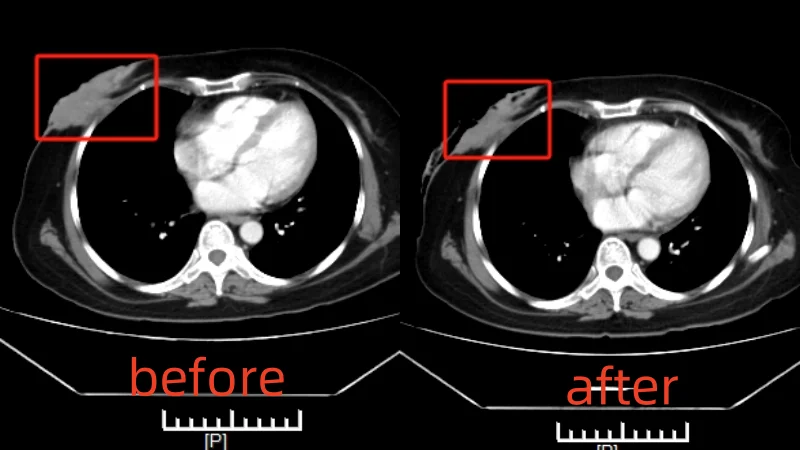

Breast Cancer Case

Venus Bernardes

Nationality: Filipino

Diagnosis: Breast cancer stage IV (invasive ductal carcinoma)

Treatment Process: In July 2023, Venus was diagnosed with invasive ductal carcinoma. Refusing chemotherapy due to concerns about side effects, she came to Guangzhou with her husband after learning about our minimally invasive technologies. The MDT team designed an interventional therapy + microwave ablation plan. After the first session, the tumor shrank from 8.5×3.2cm to 7.9×2cm.